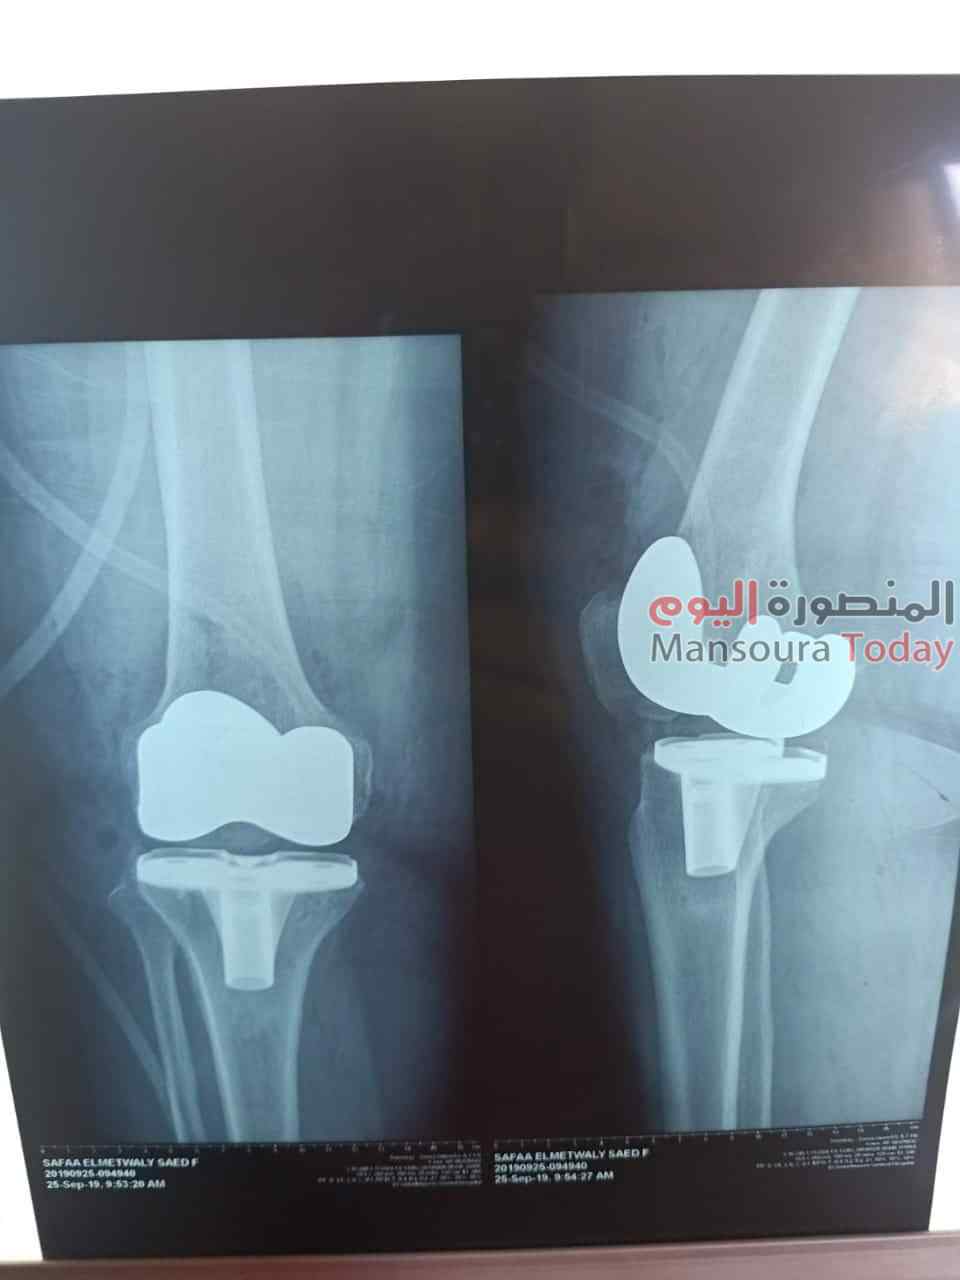

نجاح فريق طبي بتغيير مفصل ركبة كامل لمريضة بمستشفى السنبلاوين العام

أعلن الدكتور سعد مكى وكيل وزارة الصحة بالدقهلية، عن قيام فريق طبى بمستشفى السنبلاوين العام ،بإجراء جراحة دقيقة وحرجة لسيدة تبلغ من العمر 55 سنة كانت تعانى من خشونة وتقوس شديد بالركبة مما يعيق حركتها ، حيث كانت ضمن الحالات الحرجة لقوائم الإنتظار. وتمكن الفريق الطبى من إجراء تغيير كامل لمفصل الركبة على مدار ثلاث ساعات ،كما تقدم وكيل وزارة الصحة بالشكر لادارة المستشفي والفريق الطبي بقيادة الدكتور أشرف العزب متخصص في جراحات الركبة ،الدكتور أحمد صبري والدكتور عمرو فتحي أخصائي تخدير والفريق المعاون من هيئة التمريض والفنيين متمنيآ لهم المزيد من التقدم والازدهار.